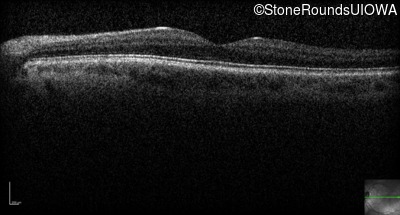

The clinical features supporting the diagnosis of congenital stationary synaptic dysfunction in this patient include: nystagmus noticed in the first year of life; reduced acuity; normal color naming; a normal fundus appearance; a normal OCT; selective loss of the b-wave on the scotopic bright flash ERG; normally sighted parents; and, a similarly affected maternal grandfather and maternal male cousin.